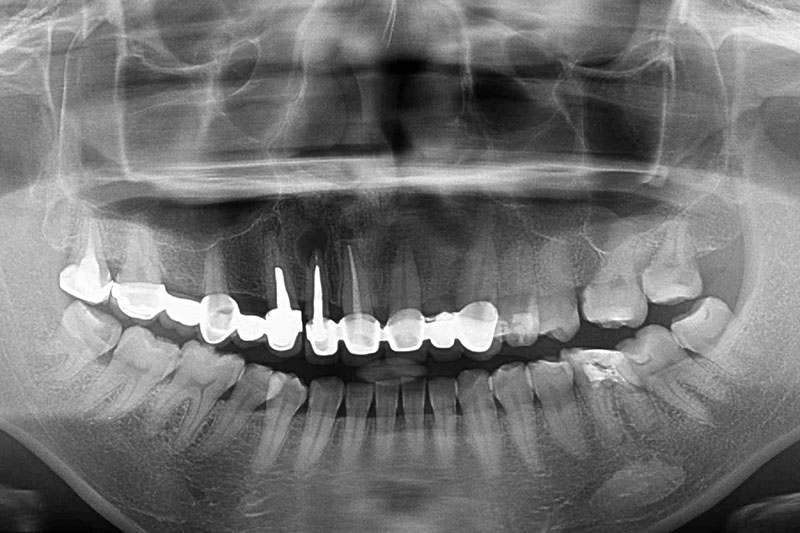

缺牙多顆-全口X光攝影

案例一

術後